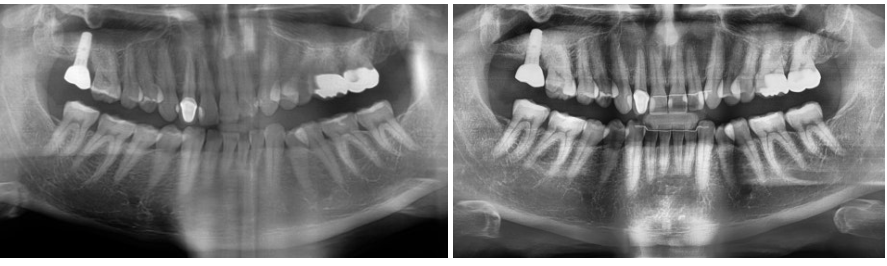

엑스레이 확인

위앞니 높이와 배열 변화 확인 가능

어금니와 기존 치아 교합은 유지